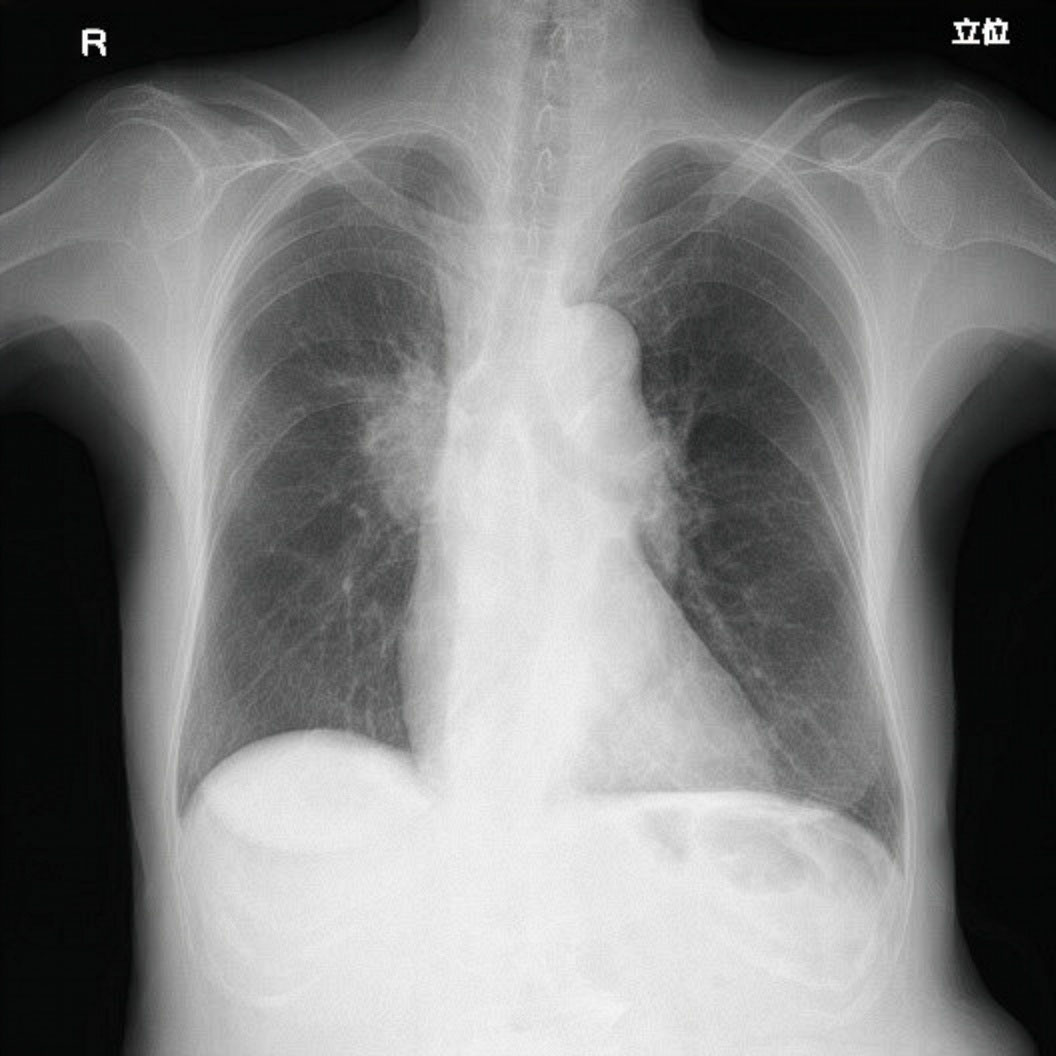

X線を用いて、人体の内部構造を画像として記録します。非侵襲的で短時間の検査が可能なのが特徴です。主な検査部位は胸部、腹部、骨、脊椎になります。

右肺腫瘍(肺癌)

一般X線撮影システム